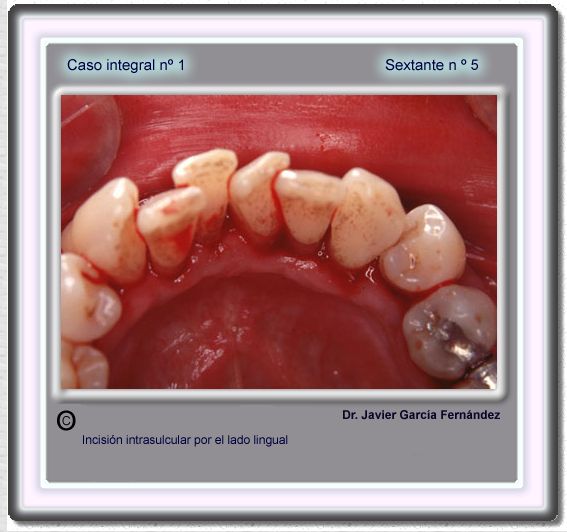

image 80